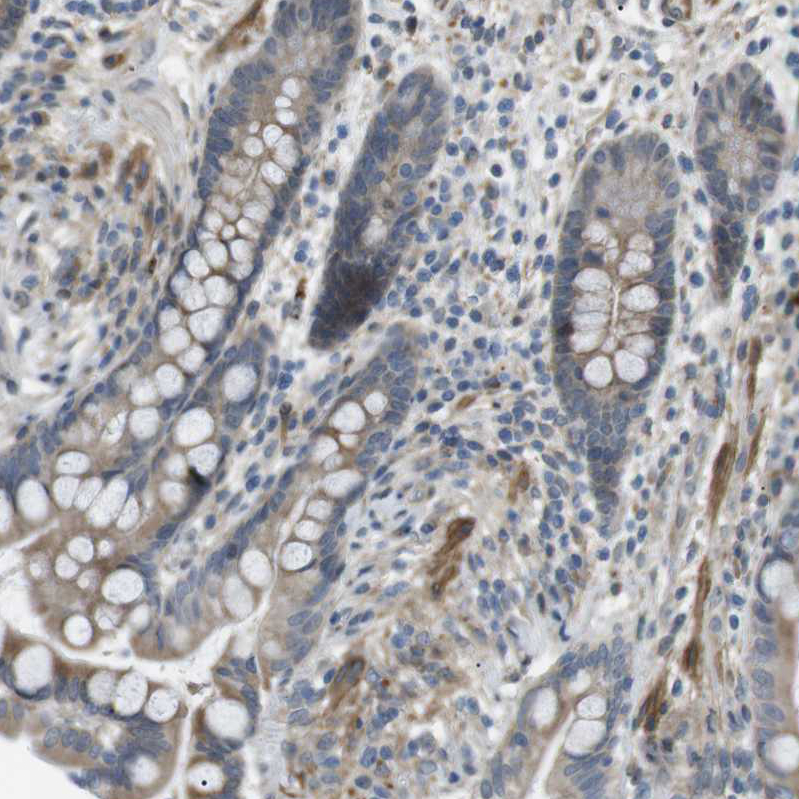

Immunohistochemical staining of human cervix shows moderate cytoplasmic positivity in squamous epithelial cells and smooth muscle cells.